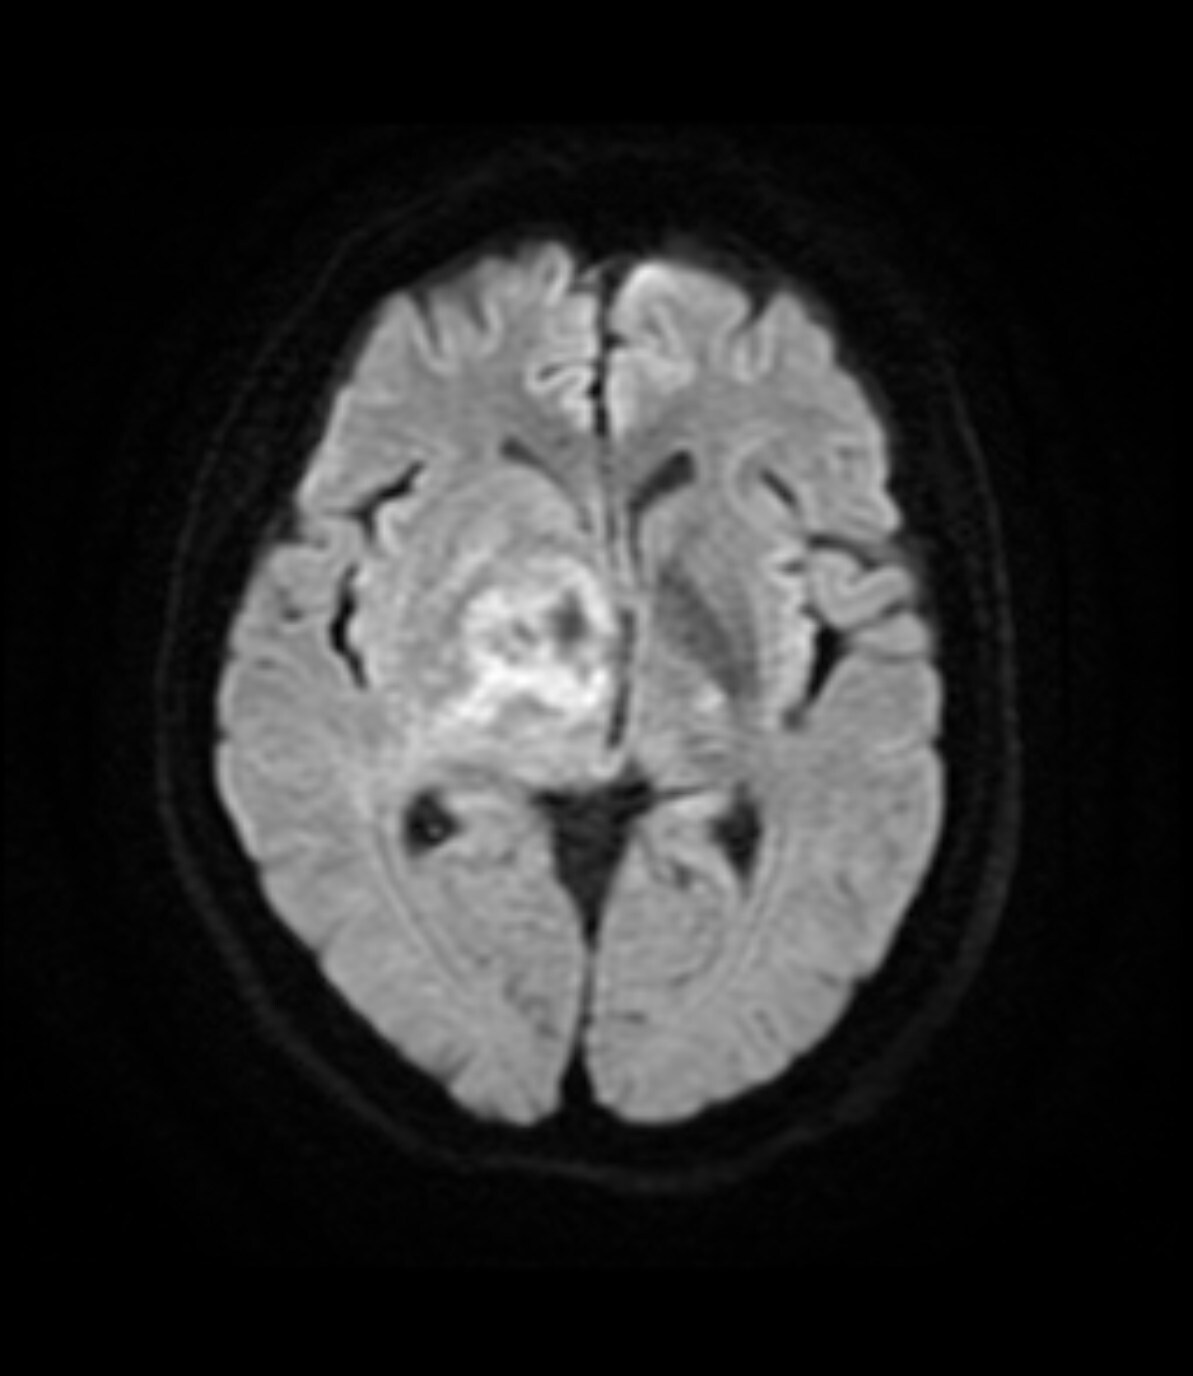

70歳代、女性、57kg、中枢神経原発悪性リンパ腫(PCNSL)

1ヶ月前から左不全麻痺、右眼瞼下垂、左同名半盲を認めた患者。近医脳外科でMRI施行し脳腫瘍を指摘されたため、当院に紹介となった。生検前の精査目的で造影MRI施行となった。

右基底核~視床~右中脳腹側にかけて均一で強いリング状増強効果を呈する腫瘤を認める。周囲に浮腫と思われるFLAIR 高信号域を認める。主病変の濃染部分はFLAIR等信号、DWI 高信号、ADCmap 低信号を呈している。MRS(TE=144)でChoが上昇、CrとNAAが低下している。ASLでは血流の顕著な上昇は認めない。中枢神経原発悪性リンパ腫(PCNSL)が疑われた。脳腫瘍生検の結果、中枢神経原発悪性リンパ腫(PCNSL)と診断された。

当該疾患の診断における造影MRIの役割

造影MRIにより腫瘍の範囲を正確に確認でき、腫瘍生検を行う際に病変を的確に捉えることができるようになると思われる。本症例のように浮腫を伴う脳腫瘍の場合、単純MRIのみでは浮腫と腫瘍の境界が不明瞭であり、腫瘍の範囲を把握するために造影MRIが必要と思われる。